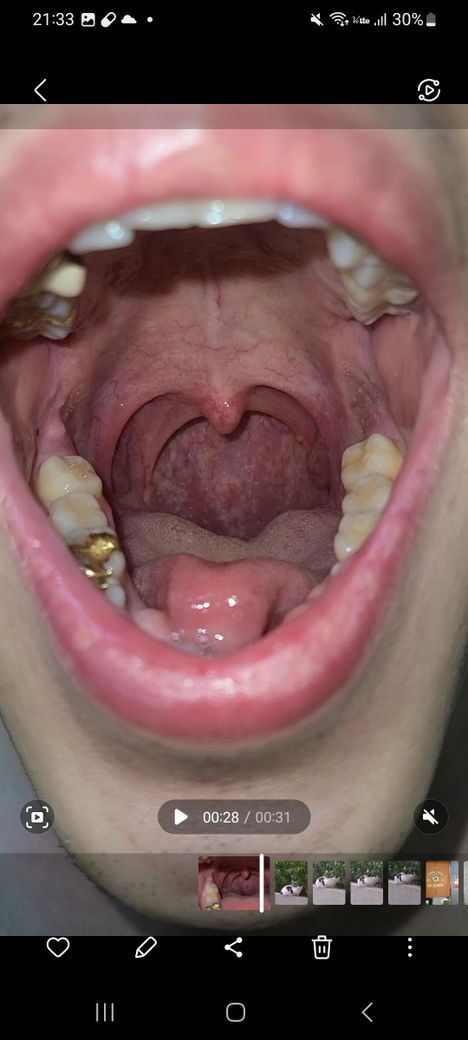

이거 편도가 부은건가요??제가 편도 비대칭인거 같은데

부은건지 모르겠지만 심한가요 상태 비대칭인데 궁금합니다 병원가야 할 정도인가요??아시는분

• 2번 째 사진

• 편도도 그렇고 몸이 완벽하게 대칭일 수는 없습니다. 사진을 통해서 보았을 때에 겉으로 보기에는 좌측의 편도가 오른쪽 보다 더 크게 보이긴 합니다만, 비정상적으로 크지 않으며 붓기가 있다고 판단할만한 소견이 따로 있어 보이지는 않습니다.